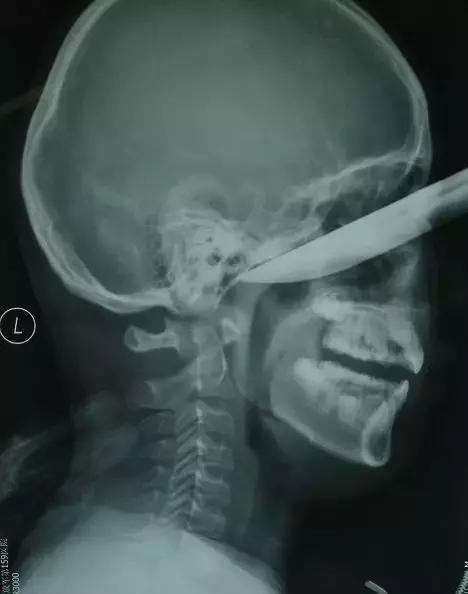

▲从眼眶进入的水果刀